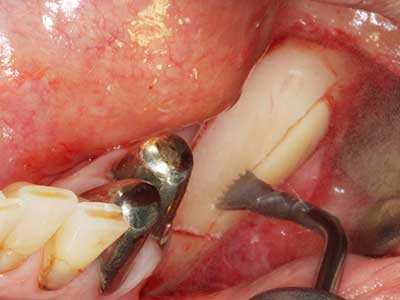

Piezo surgery has additional advantages when harvesting bone blocks. In addition to the high precision with osteotomy described above, the use of the thin saw tips specifically minimizes loss of material. Greater loss of material during harvesting can be expected with the thicker instrument tips, particularly when using Lindemann drills (Lakshmiganthan, Gokulanathan et al. 2012). The basal separation, which is necessary particularly for retromolar block transplants, is simplified by specially designed rectangular saws, with the result that piezo surgery is viewed as a precise, simple and safe procedure for harvesting retromolar bone blocks (Happe 2007) (Fig. 1-12).

Fig. 1: Preparation of a bone cover with the Piezomed (W&H Salzburg, Austria).

Fig. 3: Basal separation of the block is easier with specially angled attachments.